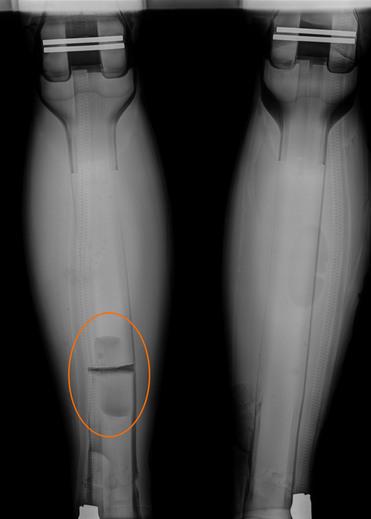

Der biofidele PRIMUS-Dummy ist der weltweit erste röntgenfähige Dummy – und genau das ist es, was den Vergleich zwischen realen und nachgestellten Verletzungen bzw. Beschädigungen so besonders macht.

Direkt nach einem Crashtest können durch medizinisches Röntgen Beschädigungen an Knochen- und Gewebeteilen des PRIMUS-Dummys sichtbar gemacht werden. Durch diese direkten Einblicke können so Rückschlüsse auf reale Verletzungen gezogen werden und ermöglichen darüber hinaus eine Einstufung in die vereinfachte Verletzungsskala (Abbreviated Injury Scale (AIS)).

Auswertung der Röntgenbilder, PRIMUS breakable

- Direktes Röntgen nach dem Crashtest

- Sofortige Visualisierung von Frakturen

- Vergleich der Beschädigungen / Verletzungen zwischen Dummy und Mensch